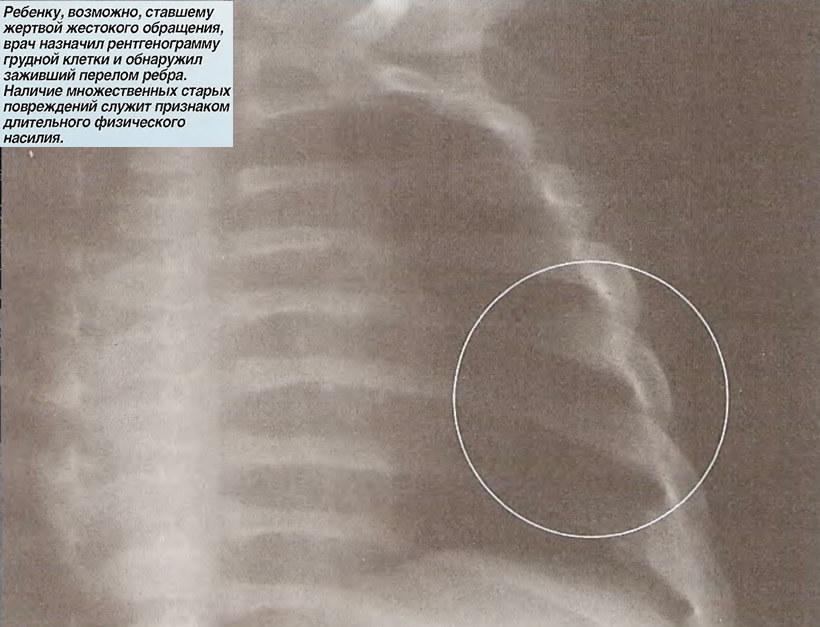

Травма органов грудной клетки на примере клинических случаев

Взгляд рентгенолога: травмы грудной клетки.